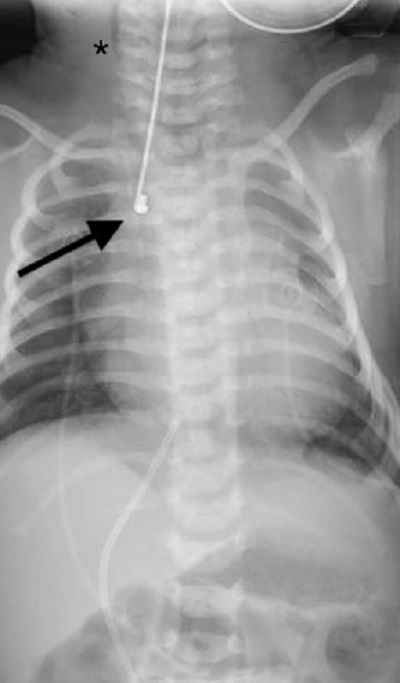

Figure 4

Case 2: Babygram showing gas in the bowel loops and a lateral position of the Replogle tube (arrow). Cervical subcutaneous emphysema is visible (*). Hyperlucency of the upper pouch is not clearly distinguishable.